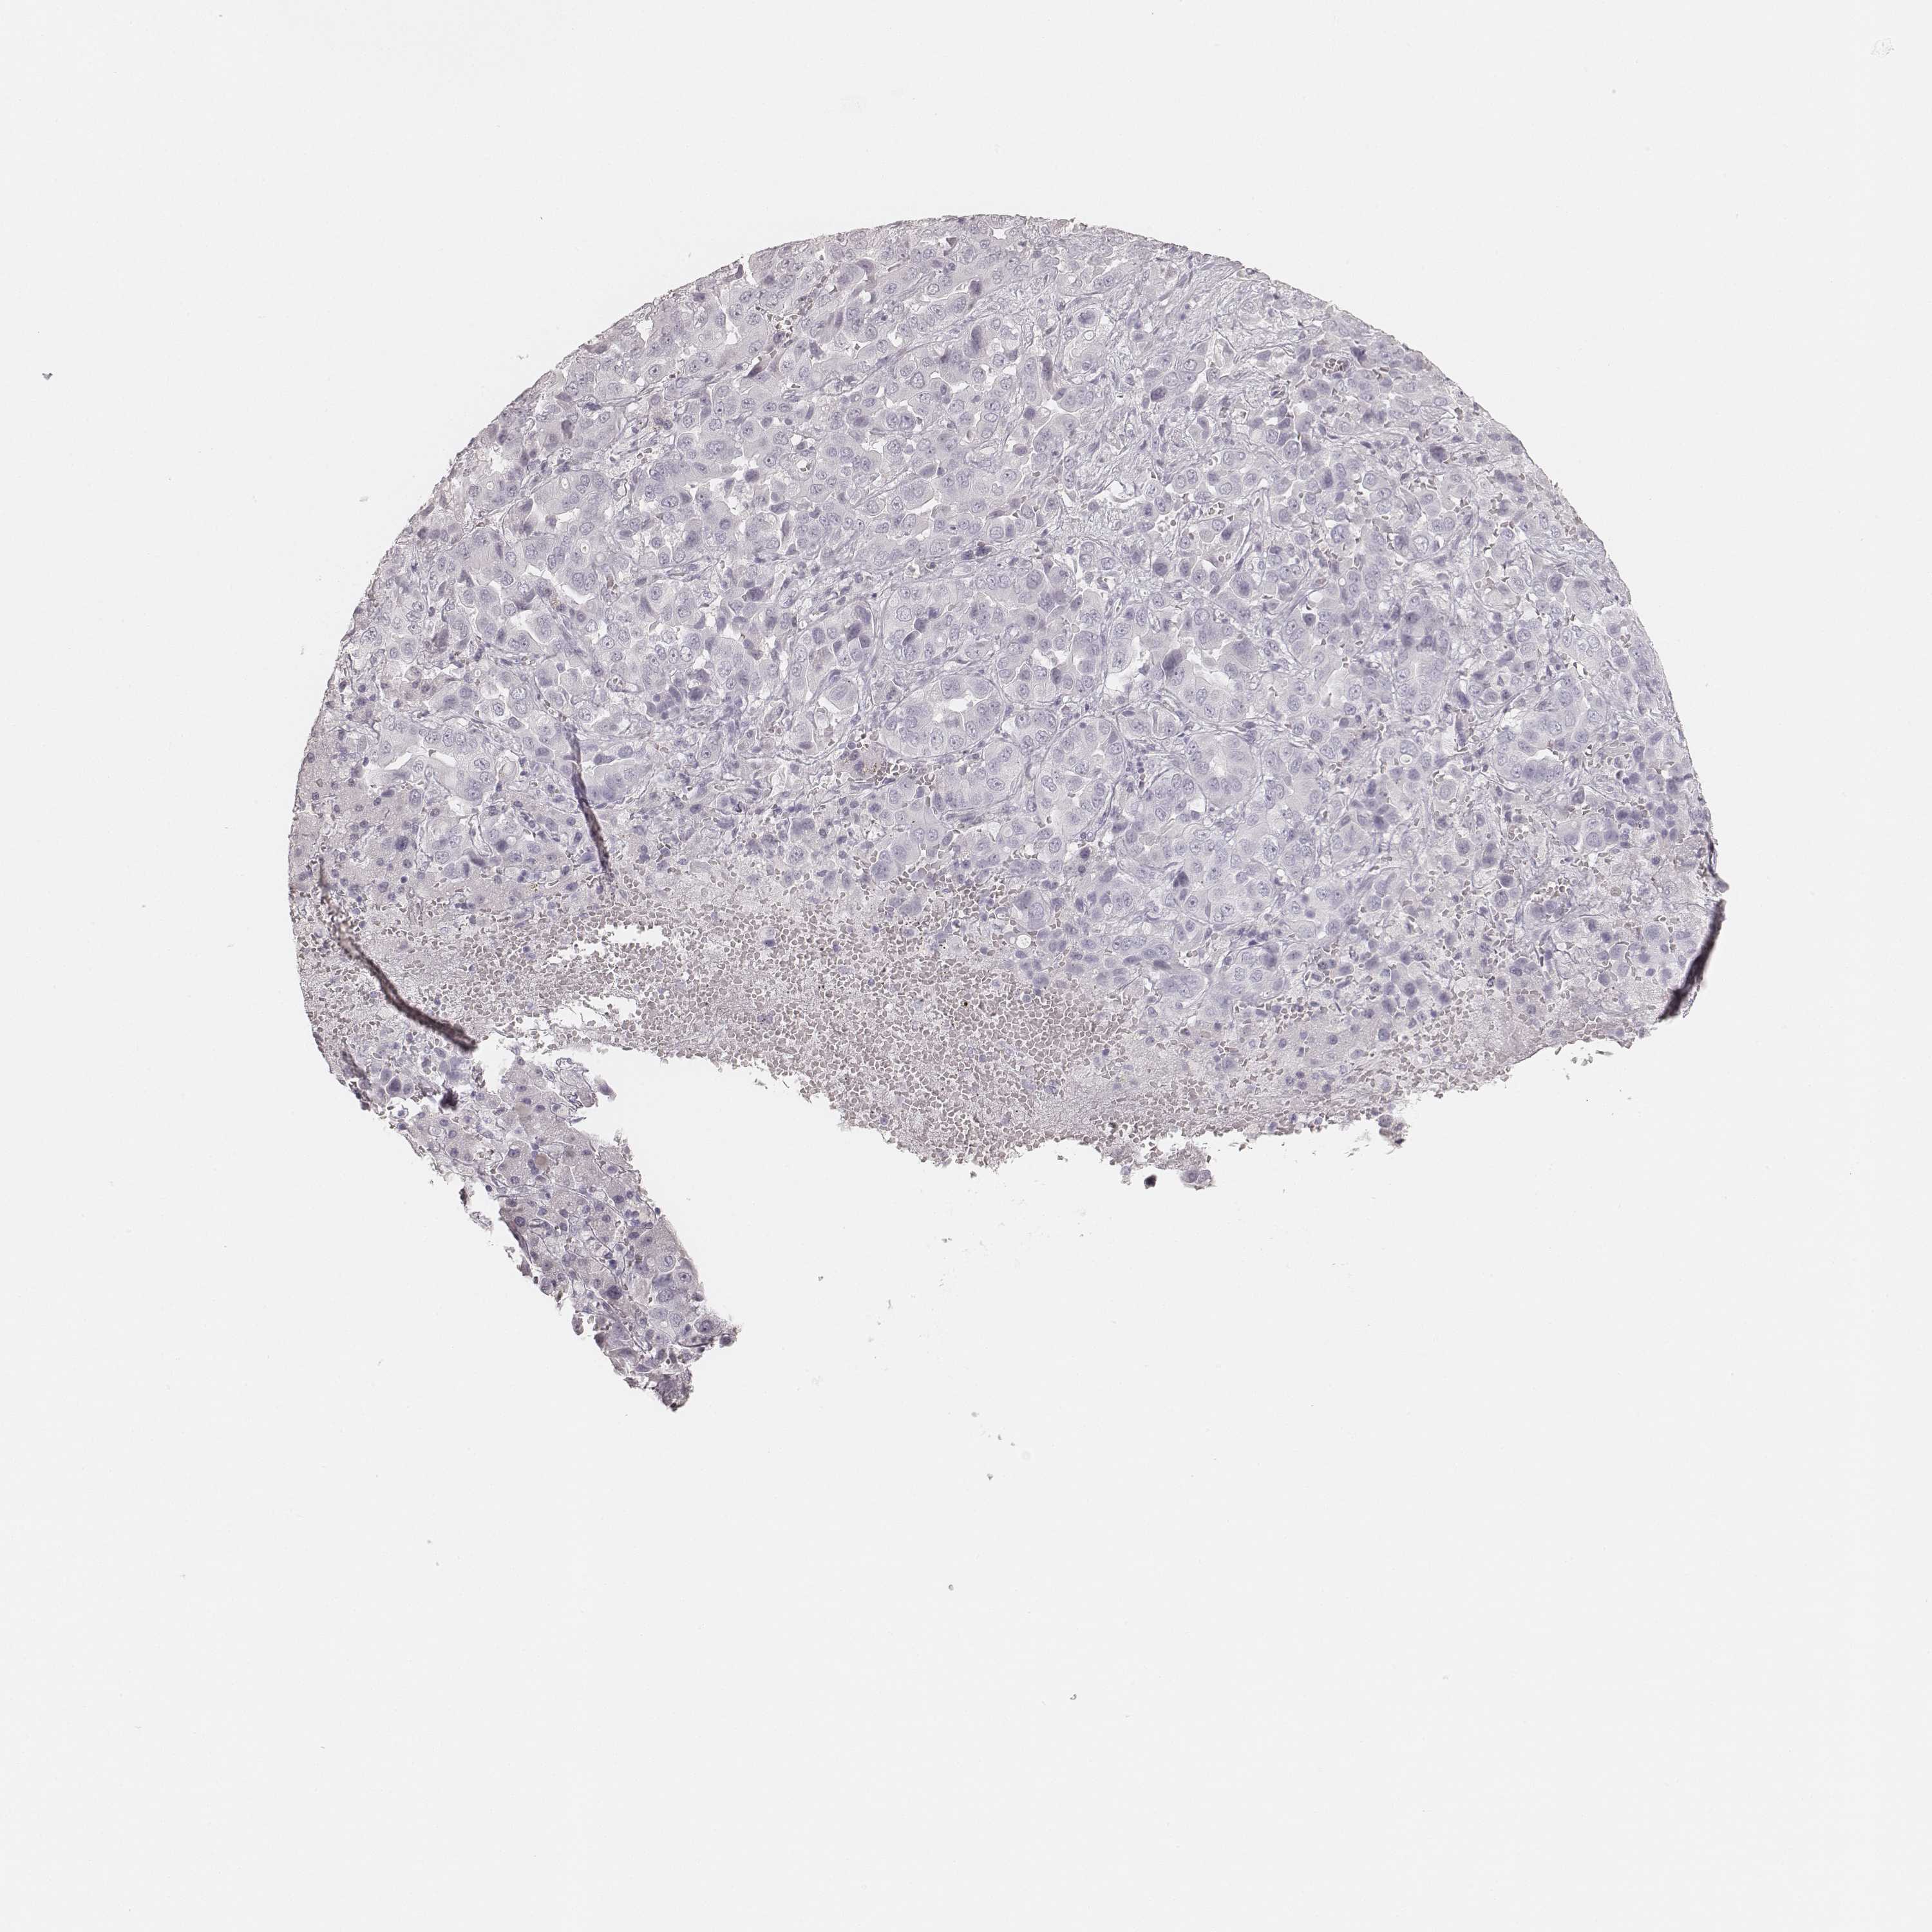

LIVER CANCER - Protein expressioni

A mouse-over function shows sample information and annotation data. Click on an image to view it in a full screen mode. Samples can be filtered based on level of antibody staining by selecting one or several of the following categories: high, medium, low and not detected. The assay and annotation is described here.

Note that samples used for immunohistochemistry by the Human Protein Atlas do not correspond to samples in the TCGA dataset.

Antibody stainingi

Antibody staining in the annotated cell types in the current human tissue is reported as not detected, low, medium, or high, based on conventional immunohistochemistry profiling in selected tissues. This score is based on the combination of the staining intensity and fraction of stained cells.

Each image is clickable and will lead to virtual microscopy that enables deeper exploration of all samples and also displays staining intensity scores, fraction scores and subcellular localization as well as patient and tissue information for each sample.

Antibody HPA049550

Antibody HPA055194

Carcinoma, Hepatocellular, NOS

Cholangiocarcinoma